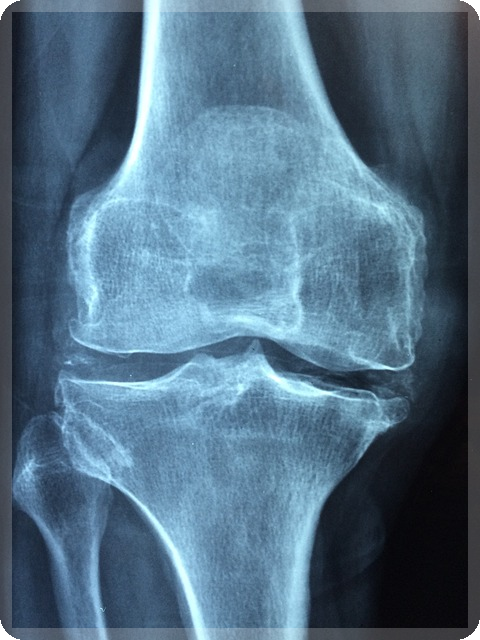

무릎 관절염은 일상생활에 큰 영향을 미치는 퇴행성 질환입니다. 관절 연골의 손상과 주변 조직의 염증으로 인해 다양한 증상이 나타나게 됩니다. 이러한 증상을 정확히 이해하고 적절한 관리를 하는 것이 중요합니다. 이번 섹션에서는 무릎 관절염의 주요 증상에 대해 알아보겠습니다.

관절 내 염증으로 인해 무릎이 붓거나 열감이 느껴질 수 있습니다. 부종은 일시적으로 나타날 수 있지만, 만성적으로 지속될 수도 있습니다. 심한 경우에는 관절액이 차는 활액막염이 발생할 수 있습니다. 시간이 지남에 따라 무릎 모양이 변형되고, O자형 또는 X자형 다리로 변화하는 경우도 있습니다. 이러한 변형은 보행 불안정성 및 추가적인 관절 손상을 초래할 수 있습니다.